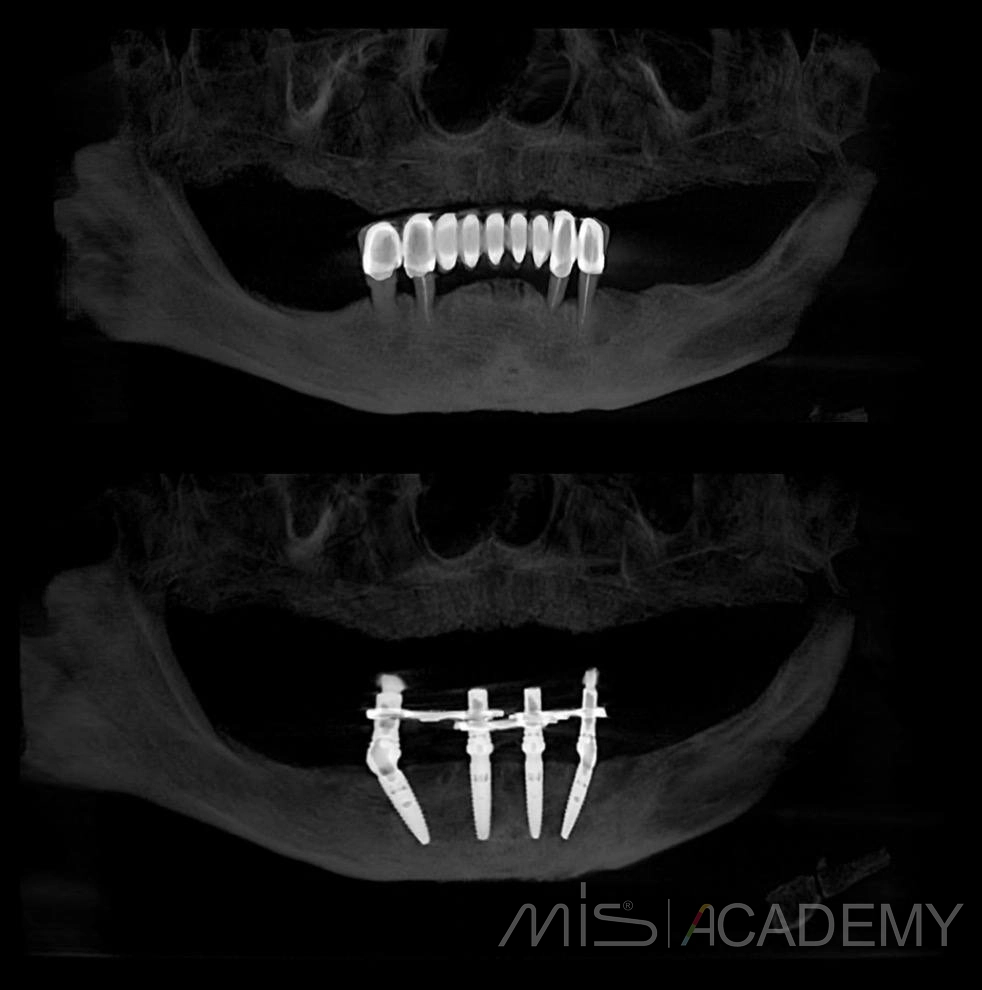

История реабилитации пациентки по протоколу на 4х имплантатах, нижняя челюсть.

Операция

3. Установка 4 имплантов MIS C1 + Multiunit.